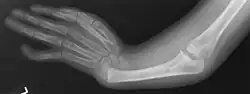

Radial ray malformations

This is characterized by hand and arm abnormalities. The following are specific characteristics:

- Malformed or absent (aplasia) thumb

- A thumb that looks more like a finger

- Partial or complete absence of a radius

- Shortening and radial deviation of the forearms

- Triphalangeal thumb

- Duplication of the thumb (preaxial polydactyly)